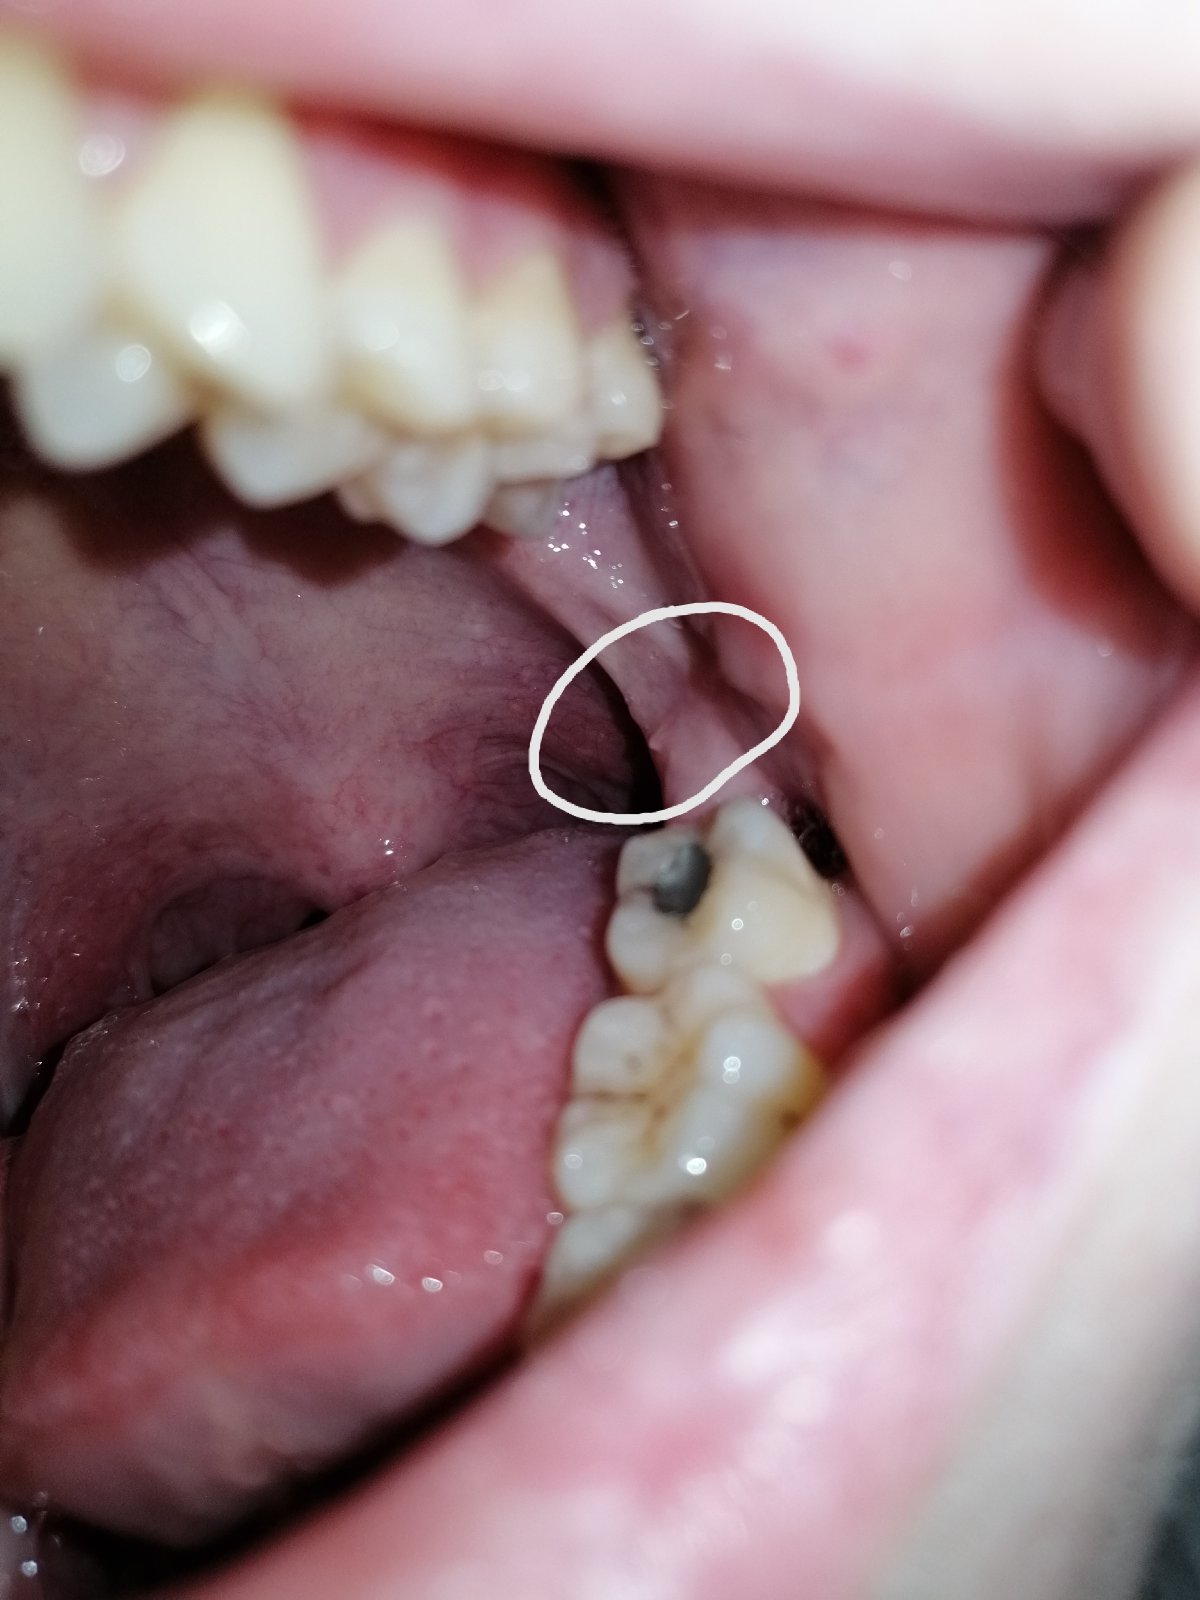

podľa fotografie sa mi nedá určiť o aký presne výrastok ide. Môže to byť zápalového pôvodu alebo polyp.

Skúste si vyplachovať ústnu dutinu roztokmi ako napr. Tantum verde alebo Garganta, pri nelepšení navštívte Vášho lekára.